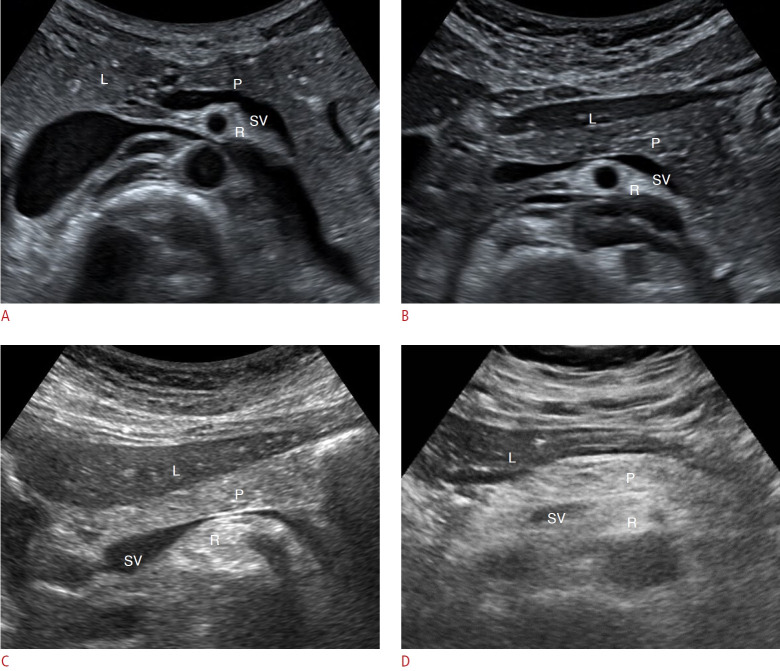

Methods: A retrospective study was conducted with 94 patients who underwent pancreatectomy between April 2006 and March 2021. The severity of HP on US was classified into two categories (normal to mild vs. moderate to severe [obvious HP]). Multiple preoperative and intraoperative parameters were analyzed to predict CR-POPF.

Results: Out of the 94 patients, CR-POPF occurred in 21 (22%) patients, and obvious HP was observed in 30 (32%). Univariate analysis revealed that moderate to severe HP (obvious HP) was significantly associated with an increased incidence of CR-POPF (P<0.001). Factors such as the absence of pancreatitis, a small main pancreatic duct (<3 mm), intraoperative soft pancreas, increased body mass index, and lower pancreatic attenuation and attenuation index were also associated with CR-POPF (all P<0.05). Multivariate analysis showed that obvious HP and soft pancreatic texture were independent predictors of CR-POPF, with odds ratios of 11.53 (P=0.001) and 14.12 (P=0.003), respectively. The combination of obvious HP and soft pancreatic texture provided the most accurate prediction for CR-POPF.

Conclusion: The severity of HP, as observed on preoperative US, was significantly associated with CR-POPF. Severe HP may serve as a clinically useful predictor of POPF, especially when evaluated alongside the intraoperative pancreatic texture.